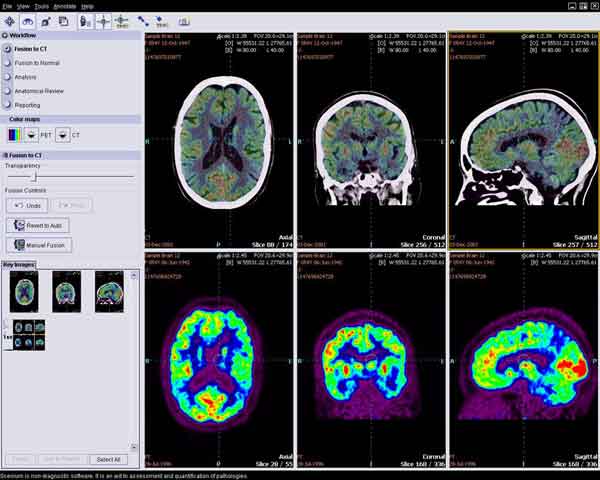

Questa ultima ricerca dimostra che un agente di imaging chiamato Florbetaben si lega direttamente alla beta-amiloide, e può essere utilizzato nell’imaging molecolare PET per visualizzare la proteina direttamente durante lo sviluppo dell’Alzheimer. Monitorando il raggruppamento e la diffusione di proteine beta-amiloide, i medici possono seguire la progressione della malattia a livello cellulare e molecolare.

Al trial clinico hanno partecipato 81 pazienti sospettati di soffrire di Alzheimer e 69 soggetti sani, in 18 diversi centri di ricerca in tutto il mondo, tutti di età superiore ai 55 anni. I cervelli dei soggetti studiati sono stati ripresi con la PET utilizzando il Florbetaben e come riferimento è stata scelta una zona del cervello completamente priva di amiloide. I ricercatori hanno scoperto che la loro tecnica era efficace nella diagnosi dell’Alzheimer sia visivamente che quantitativamente.